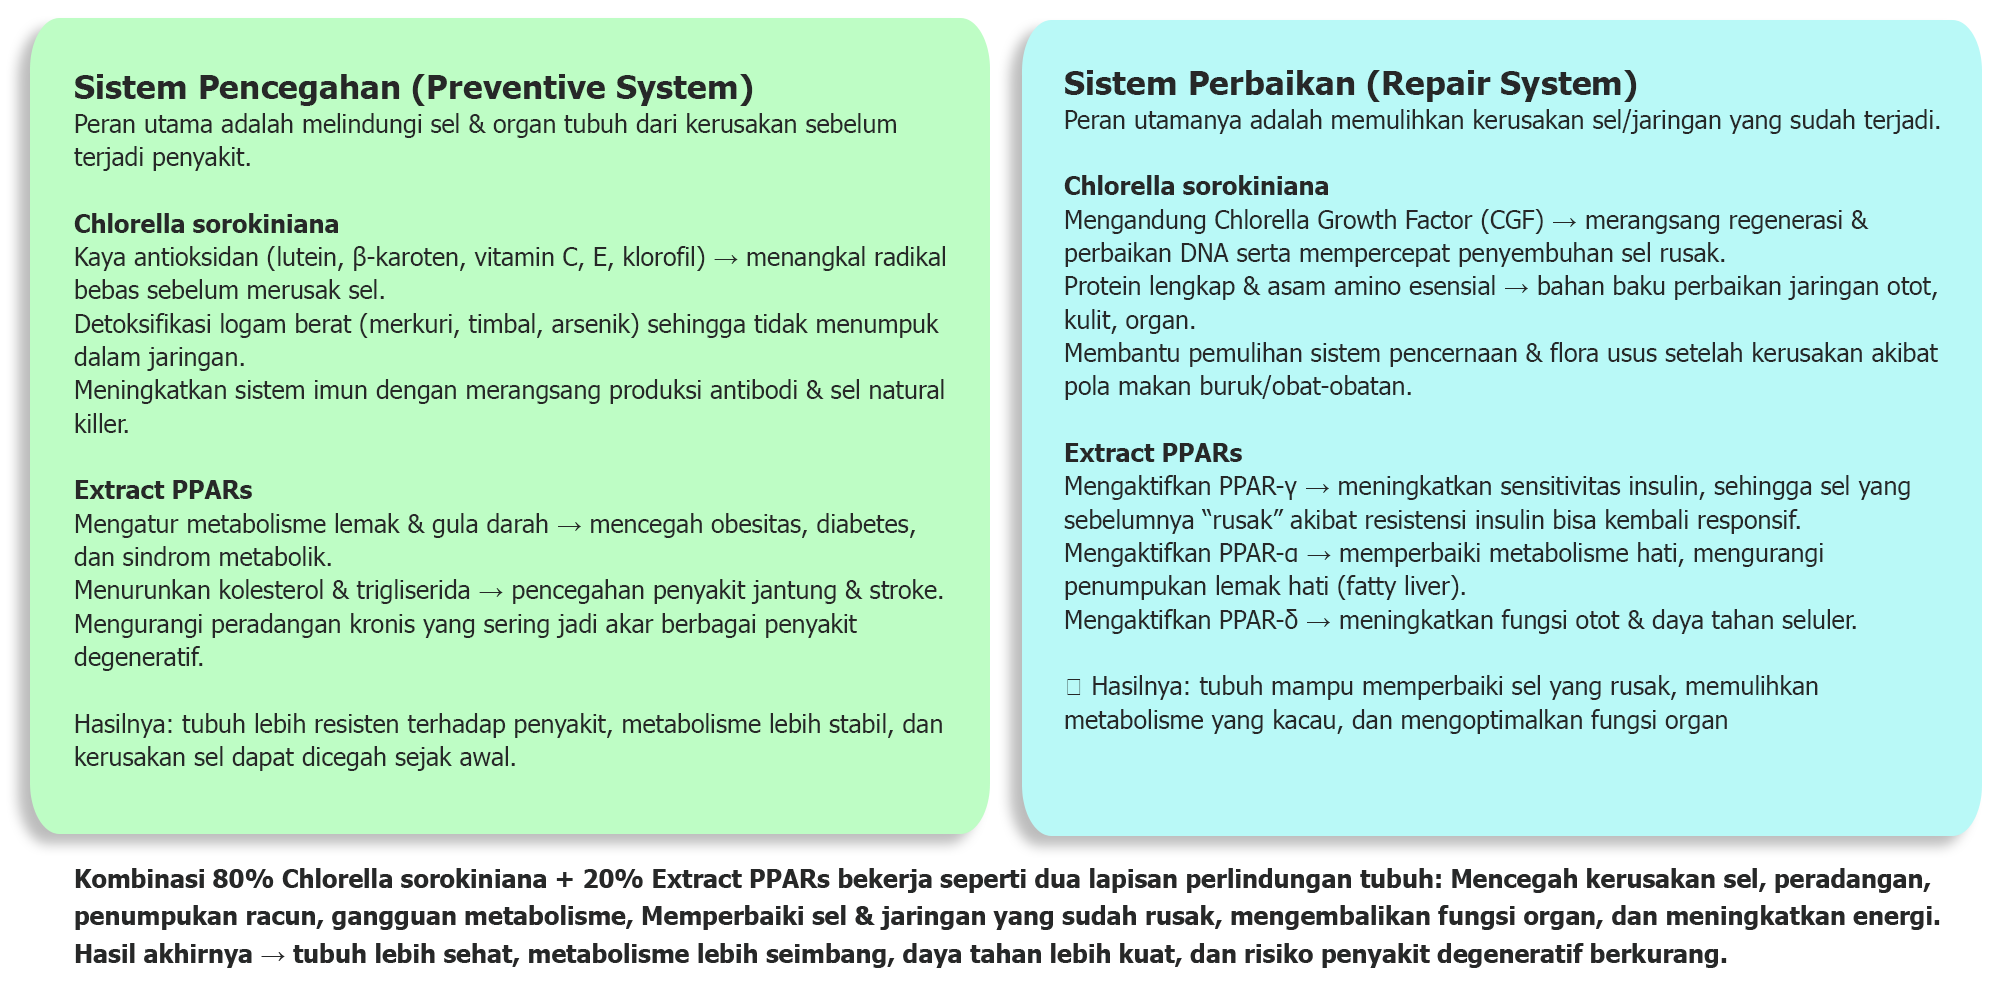

Tablet ini menggunakan 80% Chlorella Sorokiniana yaitu Jenis alga hijau biru bersel tunggal, Superfood yang sangat kaya nutrisi esensial & Antioksidan. Dan 20% Extract PPARs (Peroxisome Proliferator-Activated Receptors) adalah PPARs adalah faktor transkripsi yang diaktifkan oleh ligan yang mengatur gen penting dalam diferensisasi sel dan berbagai proses metabolisme, terutama homeostasis lipid dan gula. Simple-nya: Pengatur Metabolisme yang bermanfaat.